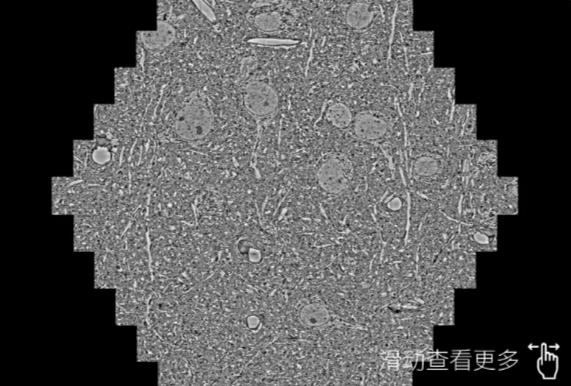

鼠脑切片。左图使用黄山蔡司黄山扫描电镜MultiSEM706对165μmx143pm面积区域成像,耗时仅需1.5秒。右图为鼠脑切片中30μm区域放大效果。样品由芝加哥大学B.Kasthuri提供。

使用蔡司高速黄山扫描电镜MultiSEM对1mm²人脑皮层组织进行高分辨成像,并对其中的各种细胞结构进行三维重构分析。左图展示了2x3mm²组织平面中锥体神经元的三维重构效果。右图显示了局部体积神经元三维重构。图像由哈佛大学chtman实验室提供,渲染图由D. Berger 制作。